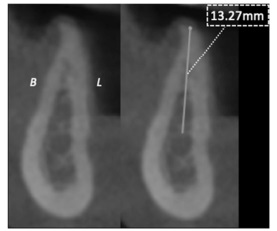

A partir da imagem e das informações precedentes, julgue o item a seguir.

A imagem apresentada permite a seleção do implante dentário e, em especial, sua extensão, considerando-se a proximidade com áreas anatômicas de risco e o baixo perfil de distorção dimensional existente nas tomografias de feixe cônico em torno de 10% da imagem real.

A partir da imagem e das informações precedentes, julgue o item a seguir.

A reconstrução axial dos arcos dentários oferece a possibilidade de análise da distribuição de implantes, conforme a configuração do padrão de crescimento mandibular, sendo maior a quantidade de implantes para o arco em forma de U invertido.

A partir da imagem e das informações precedentes, julgue o item a seguir.

Um parâmetro determinante para o comprimento do implante é a proporção coroa-implante, para o qual a biomecânica mais favorável consiste no comprimento da coroa menor que o do implante.